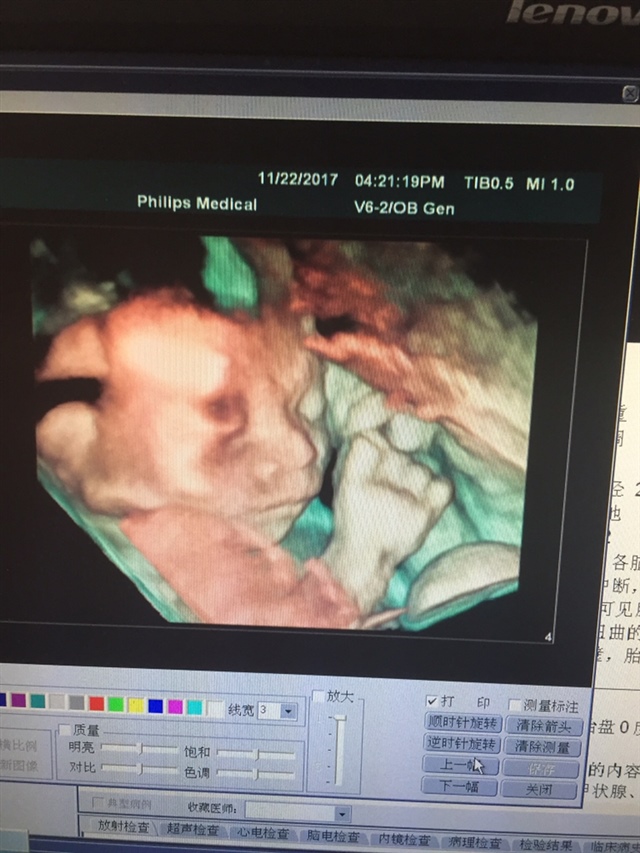

孕12周+0天

孕11周+3天

真的很清楚

拍的好清楚啊